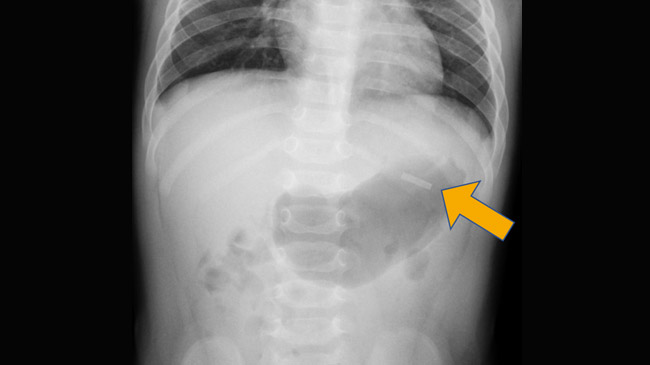

Un caso riguarda una neonata di 7 mesi. La bimba è stata portata al Pronto soccorso per sospetta ingestione di stick Terea anche se non presentava alcun sintomo legato all’avvelenamento da nicotina; la radiografia, poi, ha individuato la lamella nella seconda parte del duodeno (nessuna traccia invece dello stick).

Qui in alto l'immagine della radiografia alla bimba tratta dal case report (abbiamo evidenziato con una freccia la presenza della lamina). Fonte immagine: Higashi, K., Koike, Y., Sato, Y. et al. Extraction of a metallic susceptor after accidental ingestion of the heated tobacco stick TEREA™: a case report. BMC Pediatr 23, 452 (2023). Licenza Creative Commons

A quel punto, per la rimozione della lamina, la bambina è stata sottoposta a endoscopia, avvenuta per fortuna senza problemi. Consideriamo comunque che l’endoscopia, non è un intervento da prendere alla leggera, in particolare per un neonato: avviene attraverso una sorta di tubo, piuttosto lungo, che viene introdotto dalla bocca e permette di vedere e intervenire lungo il tratto digerente fino all’intestino.